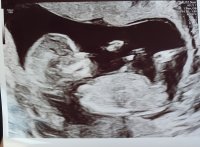

9+5 i dag. Alt så bra ut ❤️ Vi fikk se en sprellende liten bebbis med dunkende hjerte